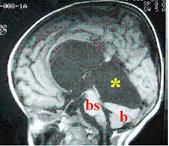

Kafa içinde araknoid zarın genişlediği, sisterna adı verilen ve Türkçe’de sarnıç anlamına gelen boşluklar bulunur. Üçüncü karıncığın arkasında ve beyinciğin üzerinde bulunan dört köşe sarnıca kuadrigeminal sisterna denir. Bu bölgede gelişen araknoid kistlere kuadrigeminal araknoid kist adı verilmektedir (Resim 7). Kuadrigeminal araknoid kistler su kanalına (aqueductus Sylvius)

Resim 7: MRG’de kuadrigeminal araknoid kist (

*) izlenmektedir. (

bs) beyin sapı, (

b) beyincik.

bası yaparak tıkanmasına ve dolayısıyla hidrosefaliye neden olurlar. Ayrıca beyin sapı ve beyinciği de bası etkileri vardır. Yakınma ve bulgular suprasellar araknoid kistlerdeki gibidir. Tedavileri şöyledir: